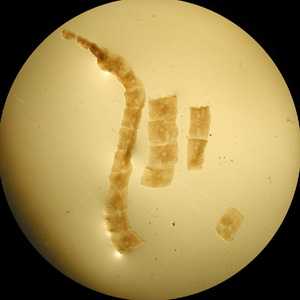

A small, cream-colored worm-like object was discovered in the diaper of a 15-month-old child. The suspect worm was collected by the child’s parents and sent to the State Health Department for identification.